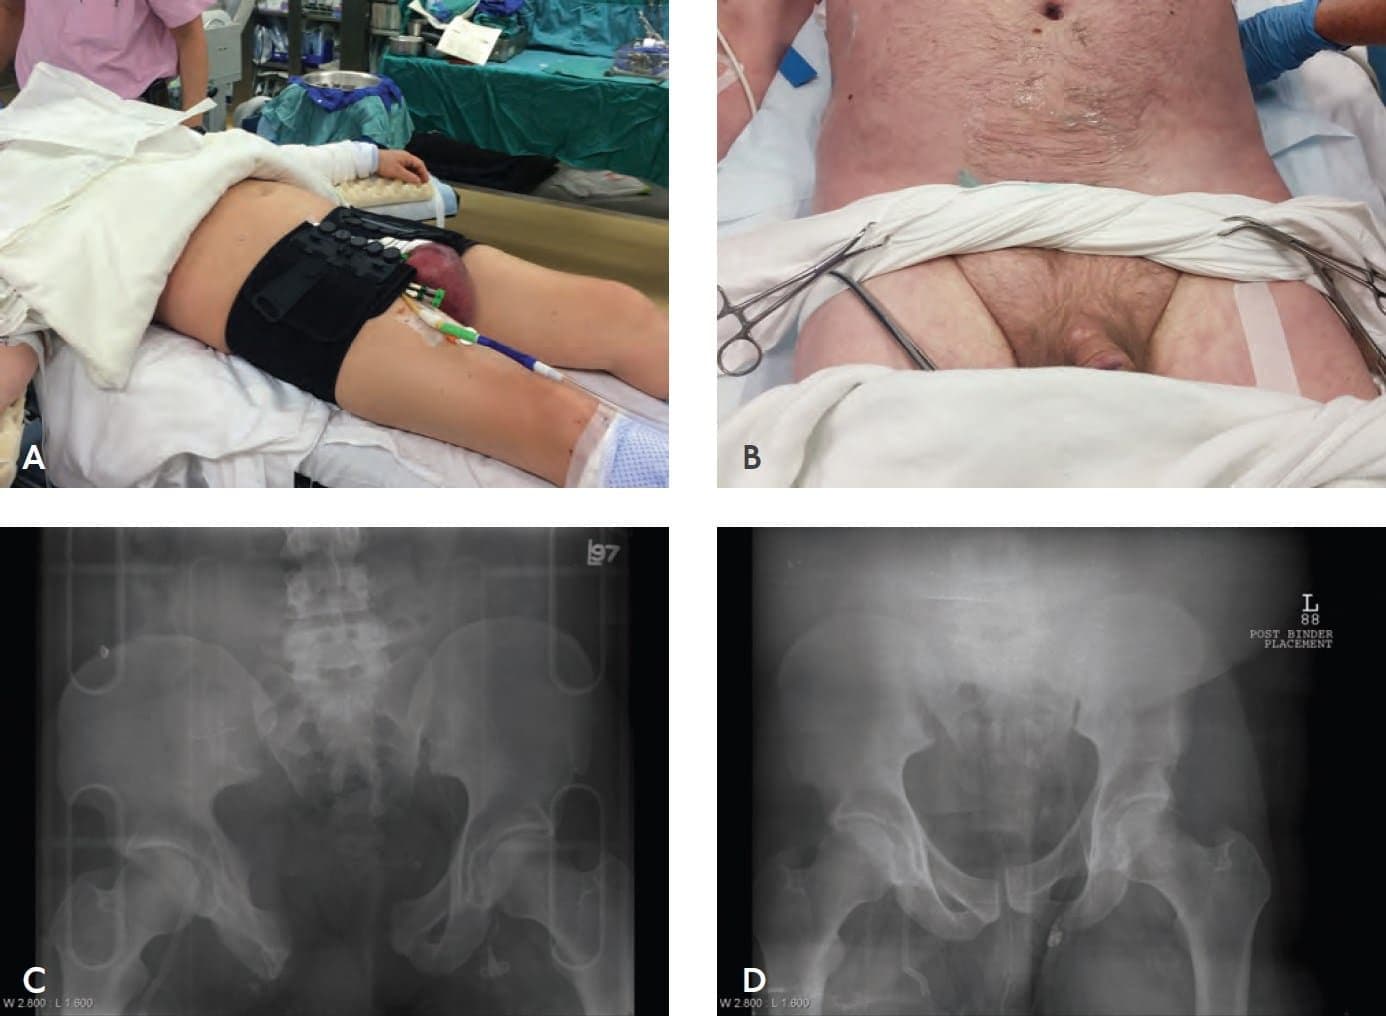

Оскільки травми тазу, пов’язані з великим крововиливом, призводять до ротації кісток тазу, внутрішня ротація нижніх кінцівок може допомогти контролювати кровотечу за рахунок зменшення об’єму тазу. Накладання шини на пошкоджений таз може зменшити потенційну тазову крововтрату. Простирадла, тазова шина або інший пристрій може забезпечити достатню тимчасову фіксацію для нестабільного тазу, якщо його накласти на рівні великих вертлюгів стегнової кістки (зобр. 5–9).

Зобр. 5–9. Стабілізація тазу.

A. Тазовий стабілізатор. B. Стабілізація тазу за допомогою простирадла.

C. Перед застосуванням тазового стабілізатора. D. Після застосування тазового стабілізатора.

Зовнішні тазові шини — це тимчасова невідкладна процедура. Правильне застосування є обов’язковим, і такі пацієнти потребують ретельного догляду. Довготривале або надто щільне розміщення апаратів фіксації тазу може спричинити пошкодження шкіри та утворення виразок над кістковими виступами.